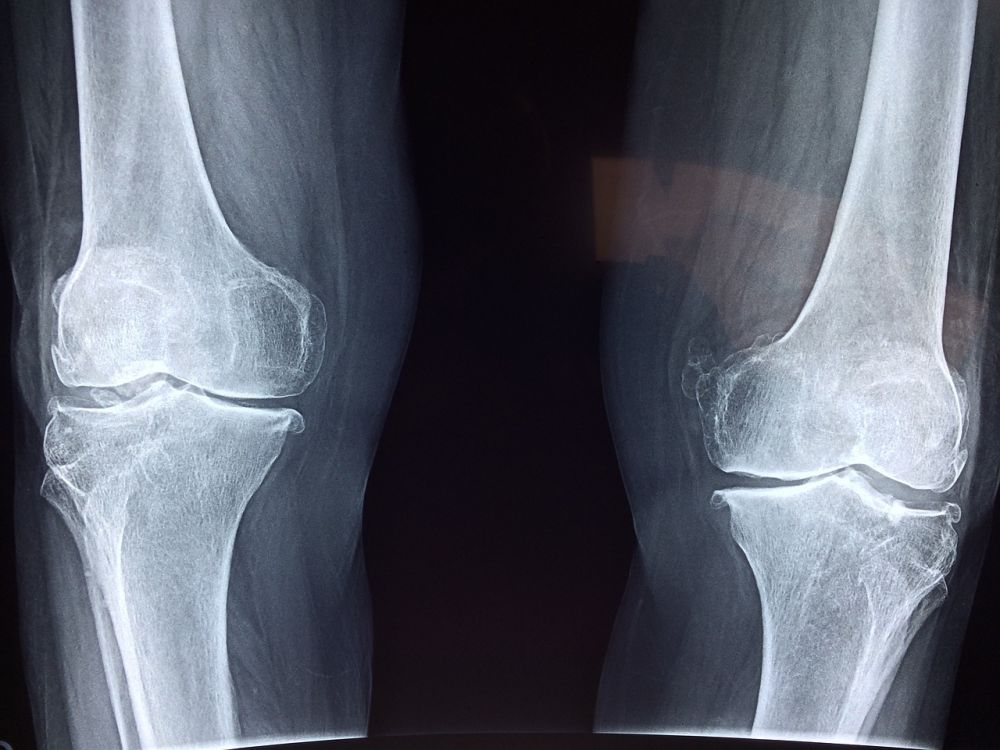

Røntgenundersøgelse

05 September 2023